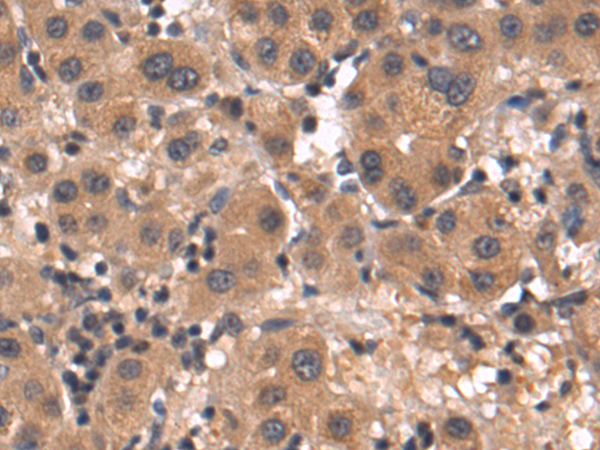

分类: 科研抗体货号: P10636别名: PI, A1A, AAT, PI1, A1AT, PRO2275, alpha1AT应用: WB,IHC反应种属: Human